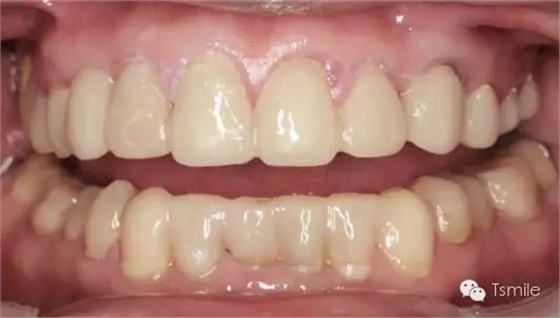

美學(xué)表達(dá)就是要把醫(yī)師大腦中形成的美學(xué)設(shè)計(jì)思想,采用各種方法準(zhǔn)確、真實(shí)、直觀地表達(dá)給患者,進(jìn)行醫(yī)患溝通,進(jìn)行口內(nèi)診斷性美學(xué)修復(fù)。在口內(nèi)根據(jù)患者主客觀反應(yīng)進(jìn)行調(diào)改,形成最終的美學(xué)修復(fù)設(shè)計(jì)。最后進(jìn)行醫(yī)技溝通,指導(dǎo)技師完成修復(fù)體制作。美學(xué)表達(dá)的方法有:數(shù)碼圖像設(shè)計(jì)(如DSD)、診斷飾面(Mock-up)、診斷蠟型(Wax-up)、模型外科、臨時(shí)修復(fù)體等。

例如面對一個(gè)牙列重度磨耗的美學(xué)修復(fù)患者,我們首先根據(jù)患者主訴和美學(xué)檢查形成美學(xué)設(shè)計(jì),然后通過數(shù)碼圖像表達(dá)美學(xué)設(shè)計(jì)思想,制作診斷蠟型,口內(nèi)制作診斷飾面,更加真實(shí)地表達(dá)美學(xué)設(shè)計(jì)。根據(jù)患者的要求和口內(nèi)試戴情況調(diào)改診斷飾面,最終確定美學(xué)修復(fù)設(shè)計(jì),即最終修復(fù)體的各種美學(xué)參數(shù)。接下來就是美學(xué)實(shí)現(xiàn)過程,在診斷飾面上進(jìn)行精確地牙體預(yù)備,制取印模和工作模型,技師按照最終診斷飾面的形態(tài)、大小和排列制作最終美學(xué)修復(fù)體,最后完成修復(fù)體粘接。